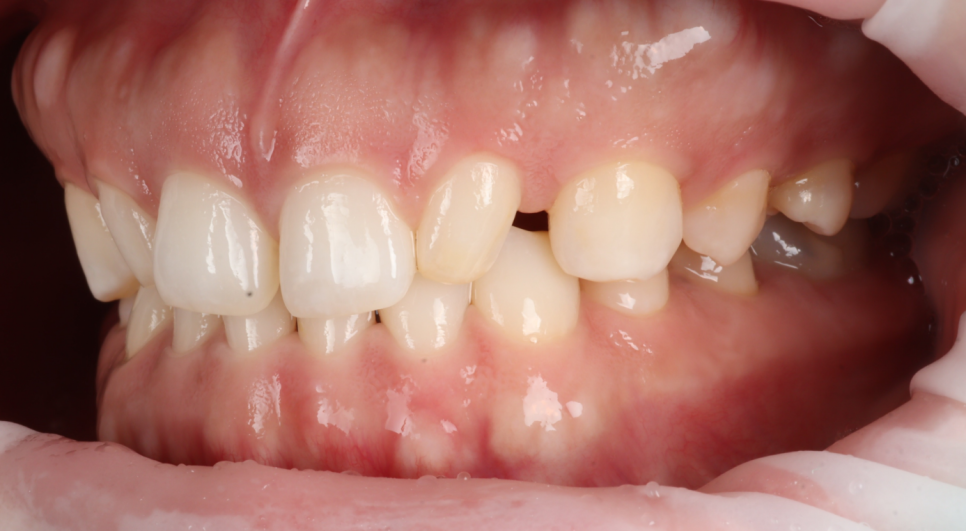

문제는 왜소치의 각도가 안쪽으로 기울어져있었다는 점입니다.

그리고 왜소치 뒤편으로 공간이 있어서 이 공간까지 메우게 되면 두 번째 앞니가 매우 커질 가능성이 있었죠.

그래서 너무 커지면 뒤쪽을 좀 삭제해서 남겨두는 방향도 설명을 드렸습니다.

환자분은 송곳니와의 사이가 벌어져 있어도 상관없다고 말씀해 주셨습니다.

먼저 요청하신 왜소치 부터 정상 비율로 만들어보고 그 비율을 기준으로 앞니 사이 공간을 어떻게 할지 결정하기로 했어요.

비율과 형태 모두 자연스러움을 목표로 했어요.

삭제는 하지 않고 반대편 측절치와 비율과 곡선만 맞추는 방식으로 진행했습니다.

이때 일부러 “사이를 완전히 꽉 채우지 않는 디자인”을 선택했는데요.

공간을 완전히 닫기보다는 소량의 여유를 남기고, 잇몸선과 치아 윤곽이 자연스럽게 이어지도록 디자인해야 잇몸 건강을 유지하기에 유리하고 위생 관리 또한 수월합니다.